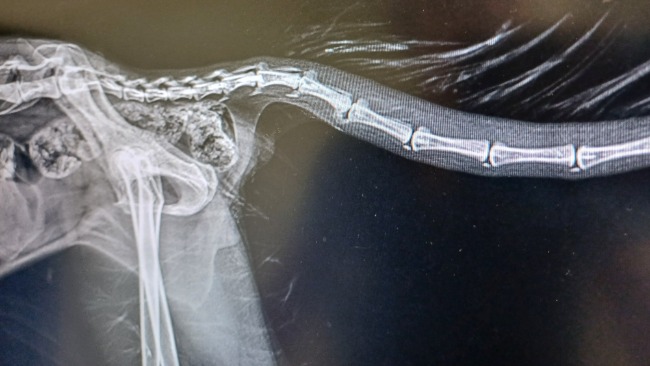

Nasz pierwszy cel zbiórki to 235 zł, na które mamy fakturę do opłacenia. Pysia była na koniecznym badaniu krwi przed zabiegiem oraz odrobaczaniu, bo jak okazało się mała ma ponownie problem z glistami. Na szczęście wszystkie wyniki krwi są w normie, więc Pysia jest gotowa na zabieg w środę!